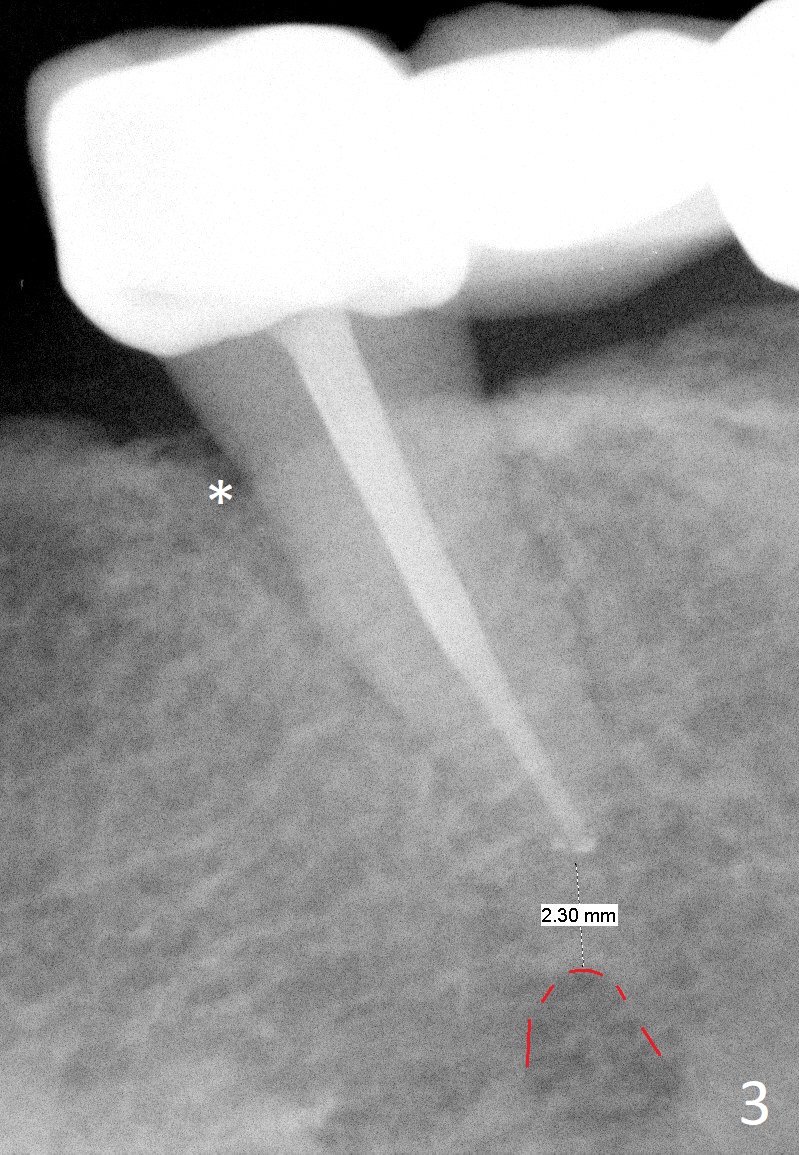

A 65-year-old woman used to have a long bridge (Fig.1). First, the portion mesial to #20 was sectioned. But the remaining portion kept chipping. RCT was retreated for the tooth #20 as the first step to have separate crowns at #18 and 20 and have a lower partial redo. Instead a new FPD was done between #18 and 20 in her own country (Fig.2). Two years later, the tooth #20 became symptomatic with increased pdl mesially (Fig.3*). Periradicular radiolucency increases in another 2 years (Fig.4). The apex of the affected tooth (yellow dashed line) is close to the Mental Loop (red dashed line, Fig.1-3). Although the loop is buccal to the apex of the 2nd premolar, an implant will not extend past the apex to avoid neuropathy (Fig.5). No Inferior Alveolar Nerve block will be administered. PA will be taken after pilot drill. The FPD will be sectioned between #18 and 19. To compensate for the short length of the implant, try to place a large one as long as the buccolingual bone allows. Adapt the lower RPD to the immediate provisional, which should be as small as possible, since the retention must be not too high.